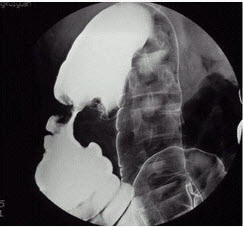

男性,50岁,触及腹部包块3周。诊断()

[单选题]男性,50岁,触及腹部包块3周。诊断:A.结肠癌B.肠结核C.溃疡性结肠炎D.正常腹平片E.肠梗阻